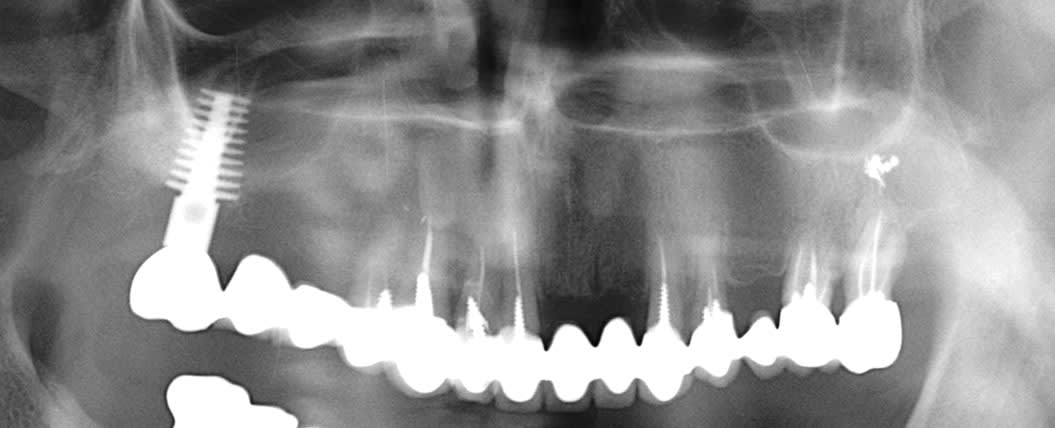

il est bien en 26 cet implant ou je me trompe?

et la 27 est bonne pour le bassinet, non?

çà va être un peu coton à gérer l'angulation de cet implant...celui qui a posé cet implant a du le faire avec la 7 taillée...je vois pas comment çà aurait pu passer autrement...(sauf si beaucoup de déformation due à la pano...)

27 a déjà jarté, j'aurais du faire la 28 dans le même temps mais elle ne me gêne pas pour l'instant.

Implant posé il y a... pfou, plus de 10 ans c'est certain, à l'époque il était solidaire de la 27.

Petite surprise à la dépose, j'y ai trouvé, entre la couronne scellée et le pilier transvissé, ce que j'ai imaginé être une chape en précieux. Surcoulée?

En antagoniste, c'est un banal stellite qui est prévu, le patient n'est pas pour l'instant emballé pour remettre le couvert en implanto, j'imaginais donc réaliser la 26 en unitaire, sans que cela ne m'emballe outre mesure.

Y'a-t-il des indications où les bridges dento implanto portés ont été validés? J'en ai vu quelques uns passer, sans que je puisse déterminer ce qui a conditionné leur réussite.

ton cas est intéressant et je ne vois pas en quoi l'implant te dérange, je crois qu'il doit mème être capable de supporter 26 et 26 (il n'y a pas 37)

Justement, c'est quoi la mécanique dans un cas comme celui-ci? Je me posais la question de solidariser 23 25 26. (et je rappelle pour info que les derniers cours dispensés en faculté sur les bridges dento implanto portés datent d'avant ma naissance)

23 est une planche pourrie, l'endo de la 14 pose question.

mais je crois que l'implant peut supporter une extension sans soucis, (c'est déjà ce qu'il a non? je crois qu'il supporte 27.

Pour la 26, prenons les choses dans l'ordre:

Si je la réalise en unitaire, j'ai peur que l'orientation des vecteurs de force masticatoire finisse par impacter la connectique implantaire (qui a certes tenu jusque là)

Si je la solidarise à 23 25, c'est le différentiel de résilience qui va finir par... par quoi au fait? Périimplantite ou descellement partiel sur l'implant j'imagine.

J'avais donc 1 idée qui me venait, là comme ça: Quid d'un système d'inlay/contre-inlay non scellé entre 25 et 26? Ca a déjà été tenté?

26 est costaud ... et pourrait servir dans un all on four...alors te prend pas le choux , si tu relie avec le bridge 23/25 ce n'est pas la peri-implantite le risque mais le bridge.

exemple d'un cas qui a plus de 25 ans pano contrôle 2008 et 2017 l'implant ne pose pas de problème